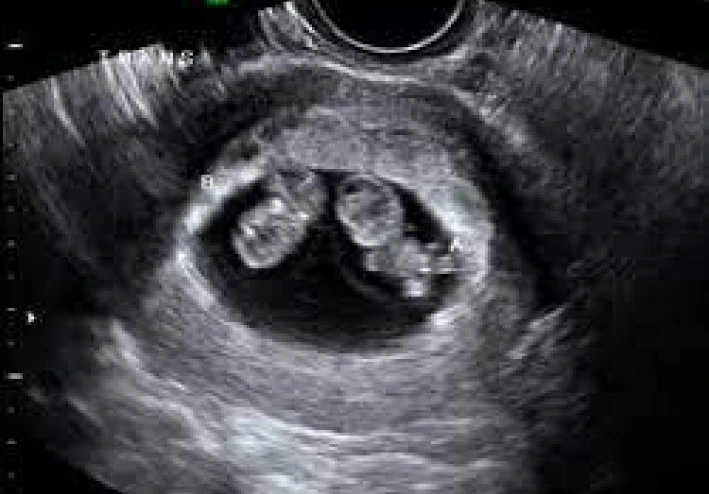

إذا كنت تريدين حقًا معرفة جنس طفلك لتقرر شيئًا مثل اختيار لون للغرفة أو شراء ملابس لطفلك مبكرًا، فالطريقة الوحيدة لتكوني دقيقًة هي الذهاب إلى الموجات فوق الصوتية.

أفضل وسيلة هي الموجات فوق الصوتية (السونار)، وعادة يمكن تحديد الجنس بدقة من الأسبوع 14 – 20 من الحمل.